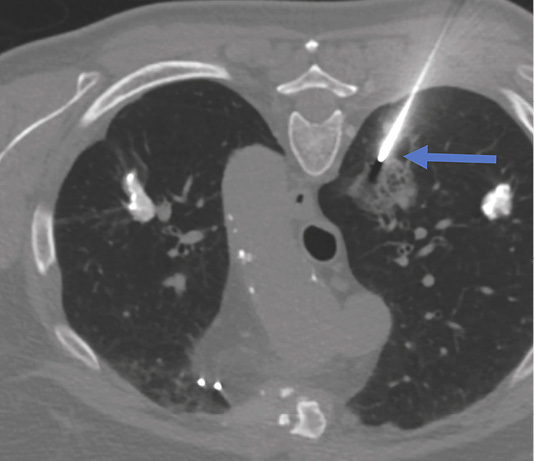

Figure 3. Head CT performed immediately after lung biopsy depicted air (white arrow) in cortical arteries in the left parietal lobe – finding representing air embolism due to lung biopsy.

Immediate head CT was performed suspecting neurological pathology. Small air foci were found in peri­pheral area of left parietal lobe – a clear sign of air embolism (Figure 3). Patient was treated with 100% oxygen.